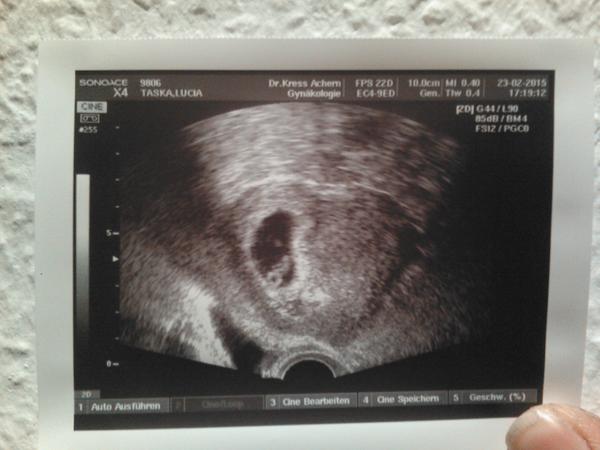

@nikuskaniki to je krasna fotka a malicky zazrak na nej...Aj je super vidiet placentu...Velmi vydareny zaber celkovo...No dalsia fotka uz bude o dost väcsia a viditelnejsie aj drobciatko 🙂...Tesim sa neskutocne, ze sa Ti splnil sen , je vidiet, ako sa tesis a ze babätko bolo silno vytuzene 😉 😘

@nikuskaniki ja mam podobnu fotku - tiez je vidiet malicke babätko a placentu (akoby kruzok dole pod babätkom - to je placenta), no Ty si 6tt.+4, ja som bola vtedy az 8tt.+1...Kuk foto 😇